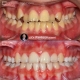

درمان ارتودنسی بدون کشیدن دندان در دختر ۱۳ ساله با مشکل نهفتگی پالاتالی دندان نیش و جلوزدگی فک بالا با forced eruption دندان نیش نهفته و استفاده از Tads system جهت دیستالیزیشن فک بالا در مدت ۲۰ ماه انجام شد.

Non extraction orthodontic treatment of 13 years old girl with palataly impacted canine and upper arch protrusion done by forced eruption of impacted canine and full upper arch distalization using Tads system within 20 months.